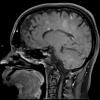

MYELIN (IMMUNE-MEDIATED)

NMO (Neuromyelitis Optica)

NMO Spectrum Disorder (8)